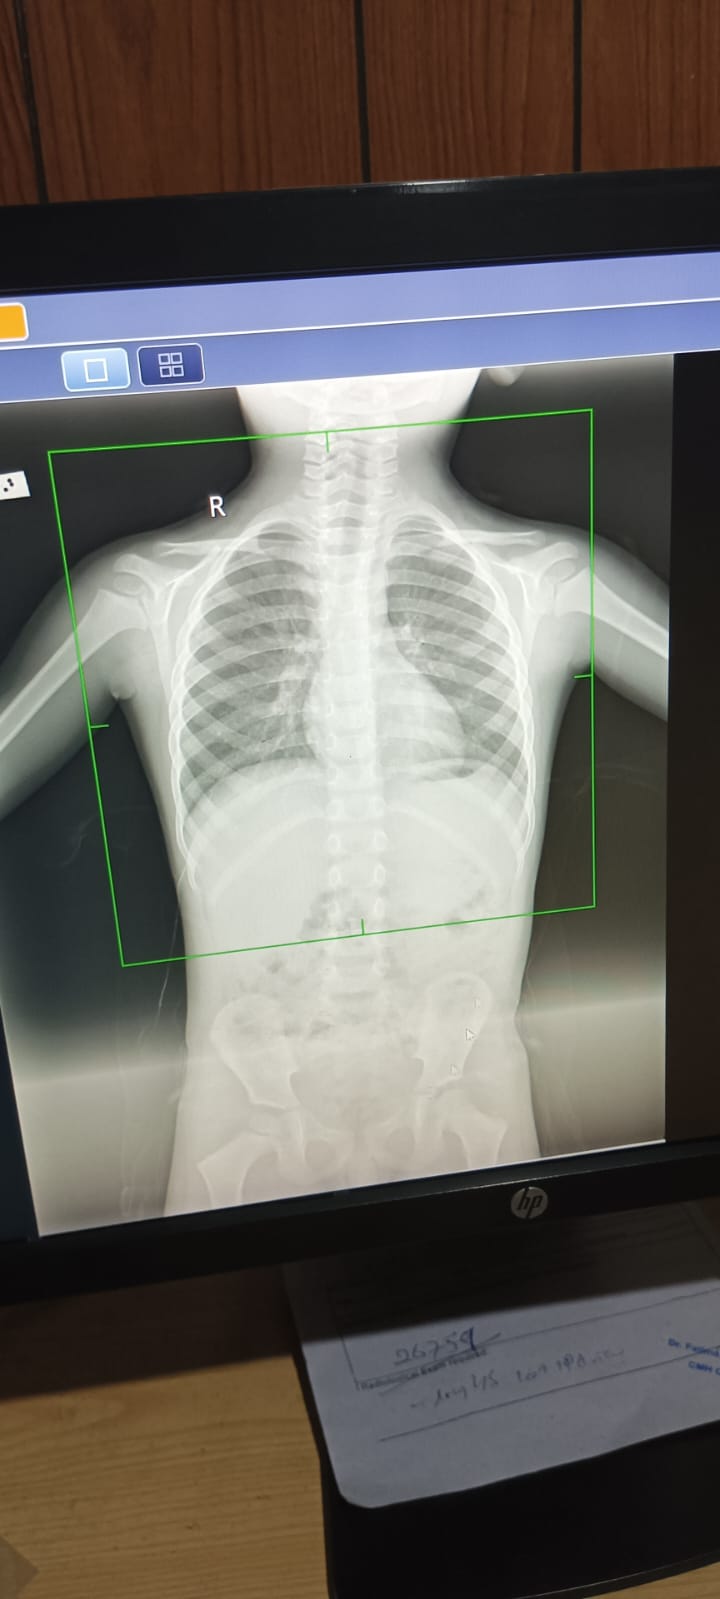

Asking for Other, Male, 4 years old, Okara

AOA Got this xray done for my son. He has cough and flu. Is it normal.

show it to the physician who advised this test for you as he knows your son's condition better than us